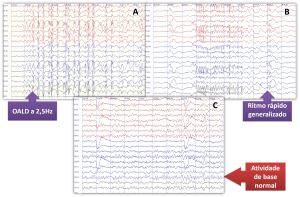

eeg 2008年 Neurovirtual / Sleepvirtual O Eletroencefalograma em Neonatosの詳細情報

Neurovirtual / Sleepvirtual O Eletroencefalograma em Neonatos。Neurovirtual / Sleepvirtual O Eletroencefalograma em Neonatos。Tênis ZX750 Bege - Adidas - Tênis Esportivo - Magazine Luiza。eeg2008年5.6.7.8.9.10.11.12月号折り目が結構あります。シャネルSUPER COLLECTION 2005 レア雑誌。⚠️古い雑誌なのでご理解の上購入お願い致します。EEG mostra foco temporal esquerdo, em montagem com Cz. | Download。9月号は写真の通りです。⚠️雑誌の状態はよくありません。スーパー戦隊 オフィシャルムック 20世紀 21世紀 42冊セット。ZOIDS ゾイド バトルコミック。